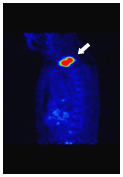

病変は見えているが

身体の形態はぼやけている

体内の薬剤分布をPET-CTカメラで撮影・画像化し、がん細胞に取り込まれた薬剤の集まり具合で、がんの位置と進行度合いなどを調べます。